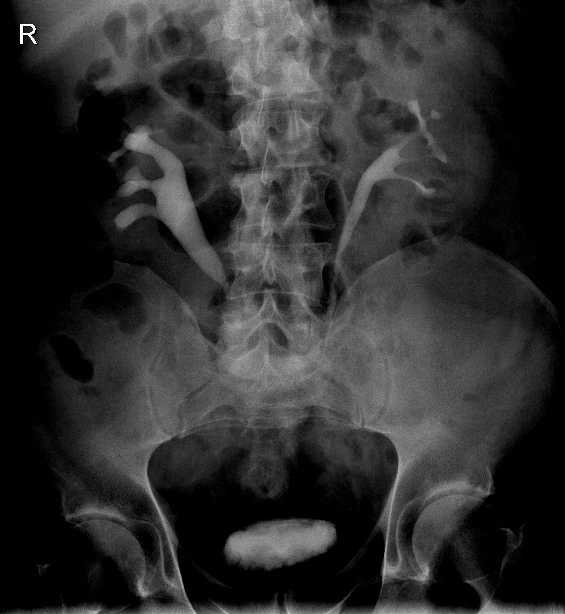

What are the imaging features of Retroperitoneal Haemorrage?

What are the HU for Acute hemorrhage?

Imaging Features